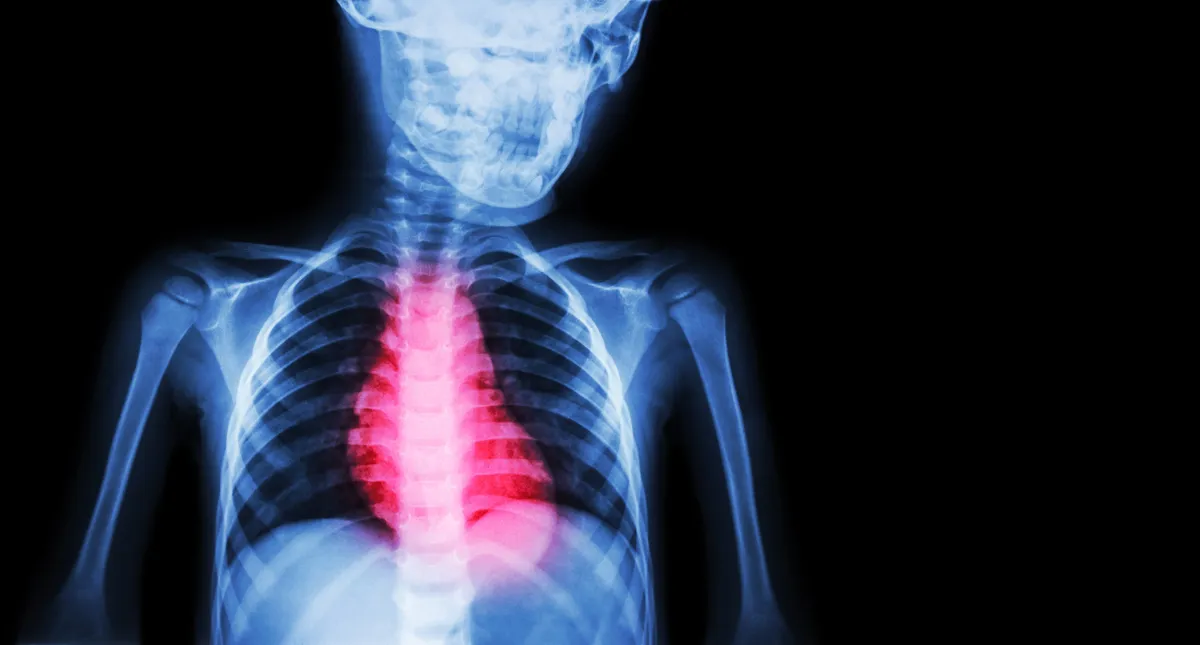

Cardiomyopathy is a disease that damages the muscle tone of the heart and reduces its ability to pump blood to the rest of the body. Cardiomyopathy is a leading cause of heart failure and the most common reason for needing a heart transplant.

Cardiomyopathies cause symptoms including shortness of breath, chest pain, fainting, dizziness and a reduced ability to exercise. In addition, people with cardiomyopathy are at increased risk of abnormal heart rhythms, or arrhythmias.